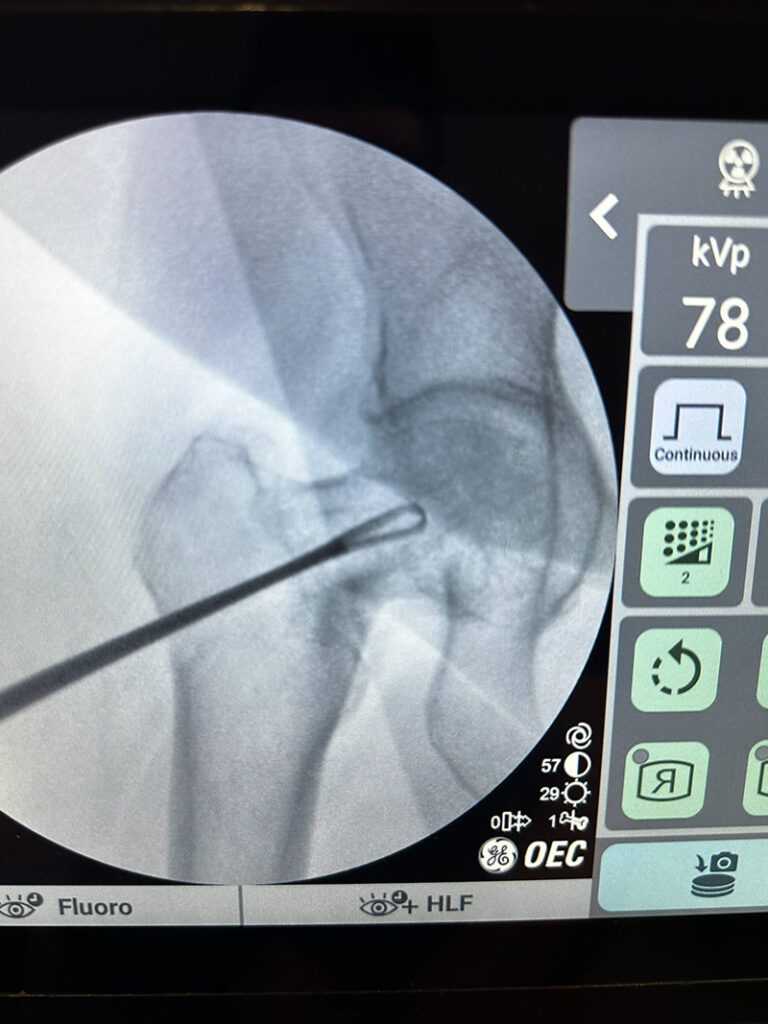

La principal ventaja de esta terapia es que se realiza con células autólogas, es decir, del propio paciente, y por lo tanto sin posibilidad de rechazo. Utilizamos un ecógrafo de alta potencia para la aplicación del producto en la zona patológica o lesionada a tratar y garantizar de esta manera una máxima eficacia.